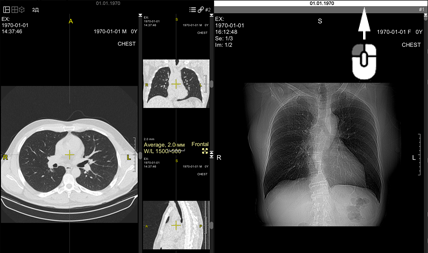

The screen will split into two parts:

The first part will contain the current study,

the second part will be about the next study in the Preview Bar